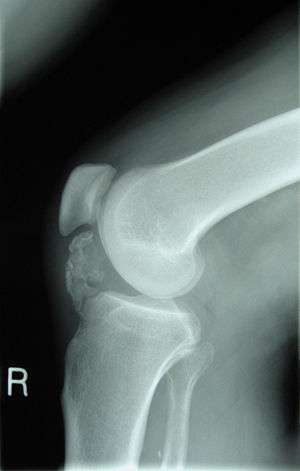

| A lateral radiograph of the knee demonstrating ossification in a patient with osteochondroma, a similar disorder. | |

This disorder is rare, and is characterised by an asymmetrical limb deformity due to localized overgrowth of cartilage, histologically resembling osteochondroma. It is believed to affect the limb bud in early fetal life. The condition occurs mostly in the ankle or knee region and it is always confined to a single limb. This usually involves only the lower extremities and on medial side of the epiphysis. It is named after researcher David Trevor.[1]

Trevor disease was first described by the French surgeon Albert Mouchet and J. Belot in 1926. In 1956, the name "dysplasia epiphysealis hemimelica" was proposed by Fairbank.[1] The usual symptoms are the appearance of an osseous protuberance, on one side of the knee, ankle or foot joint which gradually increases Radiologically,[2] the condition shows a nonuniformity of growth and multiple unconnected ossification centers around the epiphyses.[3]